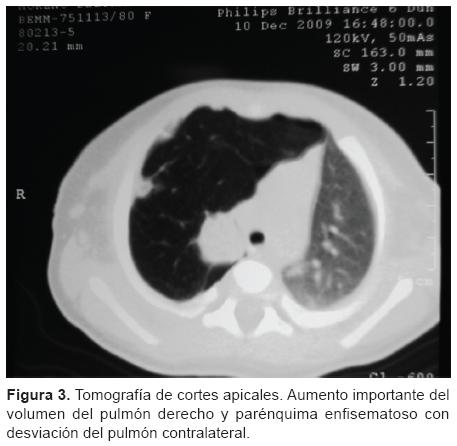

Lobar holoprosencephaly | Radiology Case | Radiopaedia.org  Congenital lobar emphysema | Eurorad

Congenital lobar emphysema | Eurorad  Lobar collapse demystified: the chest radiograph with CT correlation | Postgraduate Medical Journal

Lobar Holoprosencephaly in 2020 | Retroverted uterus, Cleft lip and palate, Cleft lip  ENFISEMA LOBAR CONGENITO PDF

ENFISEMA LOBAR CONGENITO PDF  Image | Radiopaedia.org

ENFISEMA LOBAR CONGENITO PDF  Lobar holoprosencephaly | Radiology Case | Radiopaedia.org

ENFISEMA LOBAR CONGENITO PDF  Lobar holoprosencephaly | Radiology Case | Radiopaedia.org

ENFISEMA LOBAR CONGENITO PDF  (PDF) Stereotactic Cortical Atlas of the Domestic Canine Brain

ENFISEMA LOBAR CONGENITO PDF  A case of lobar holoprosencephaly in neonatus one-month old who | Download Scientific Diagram